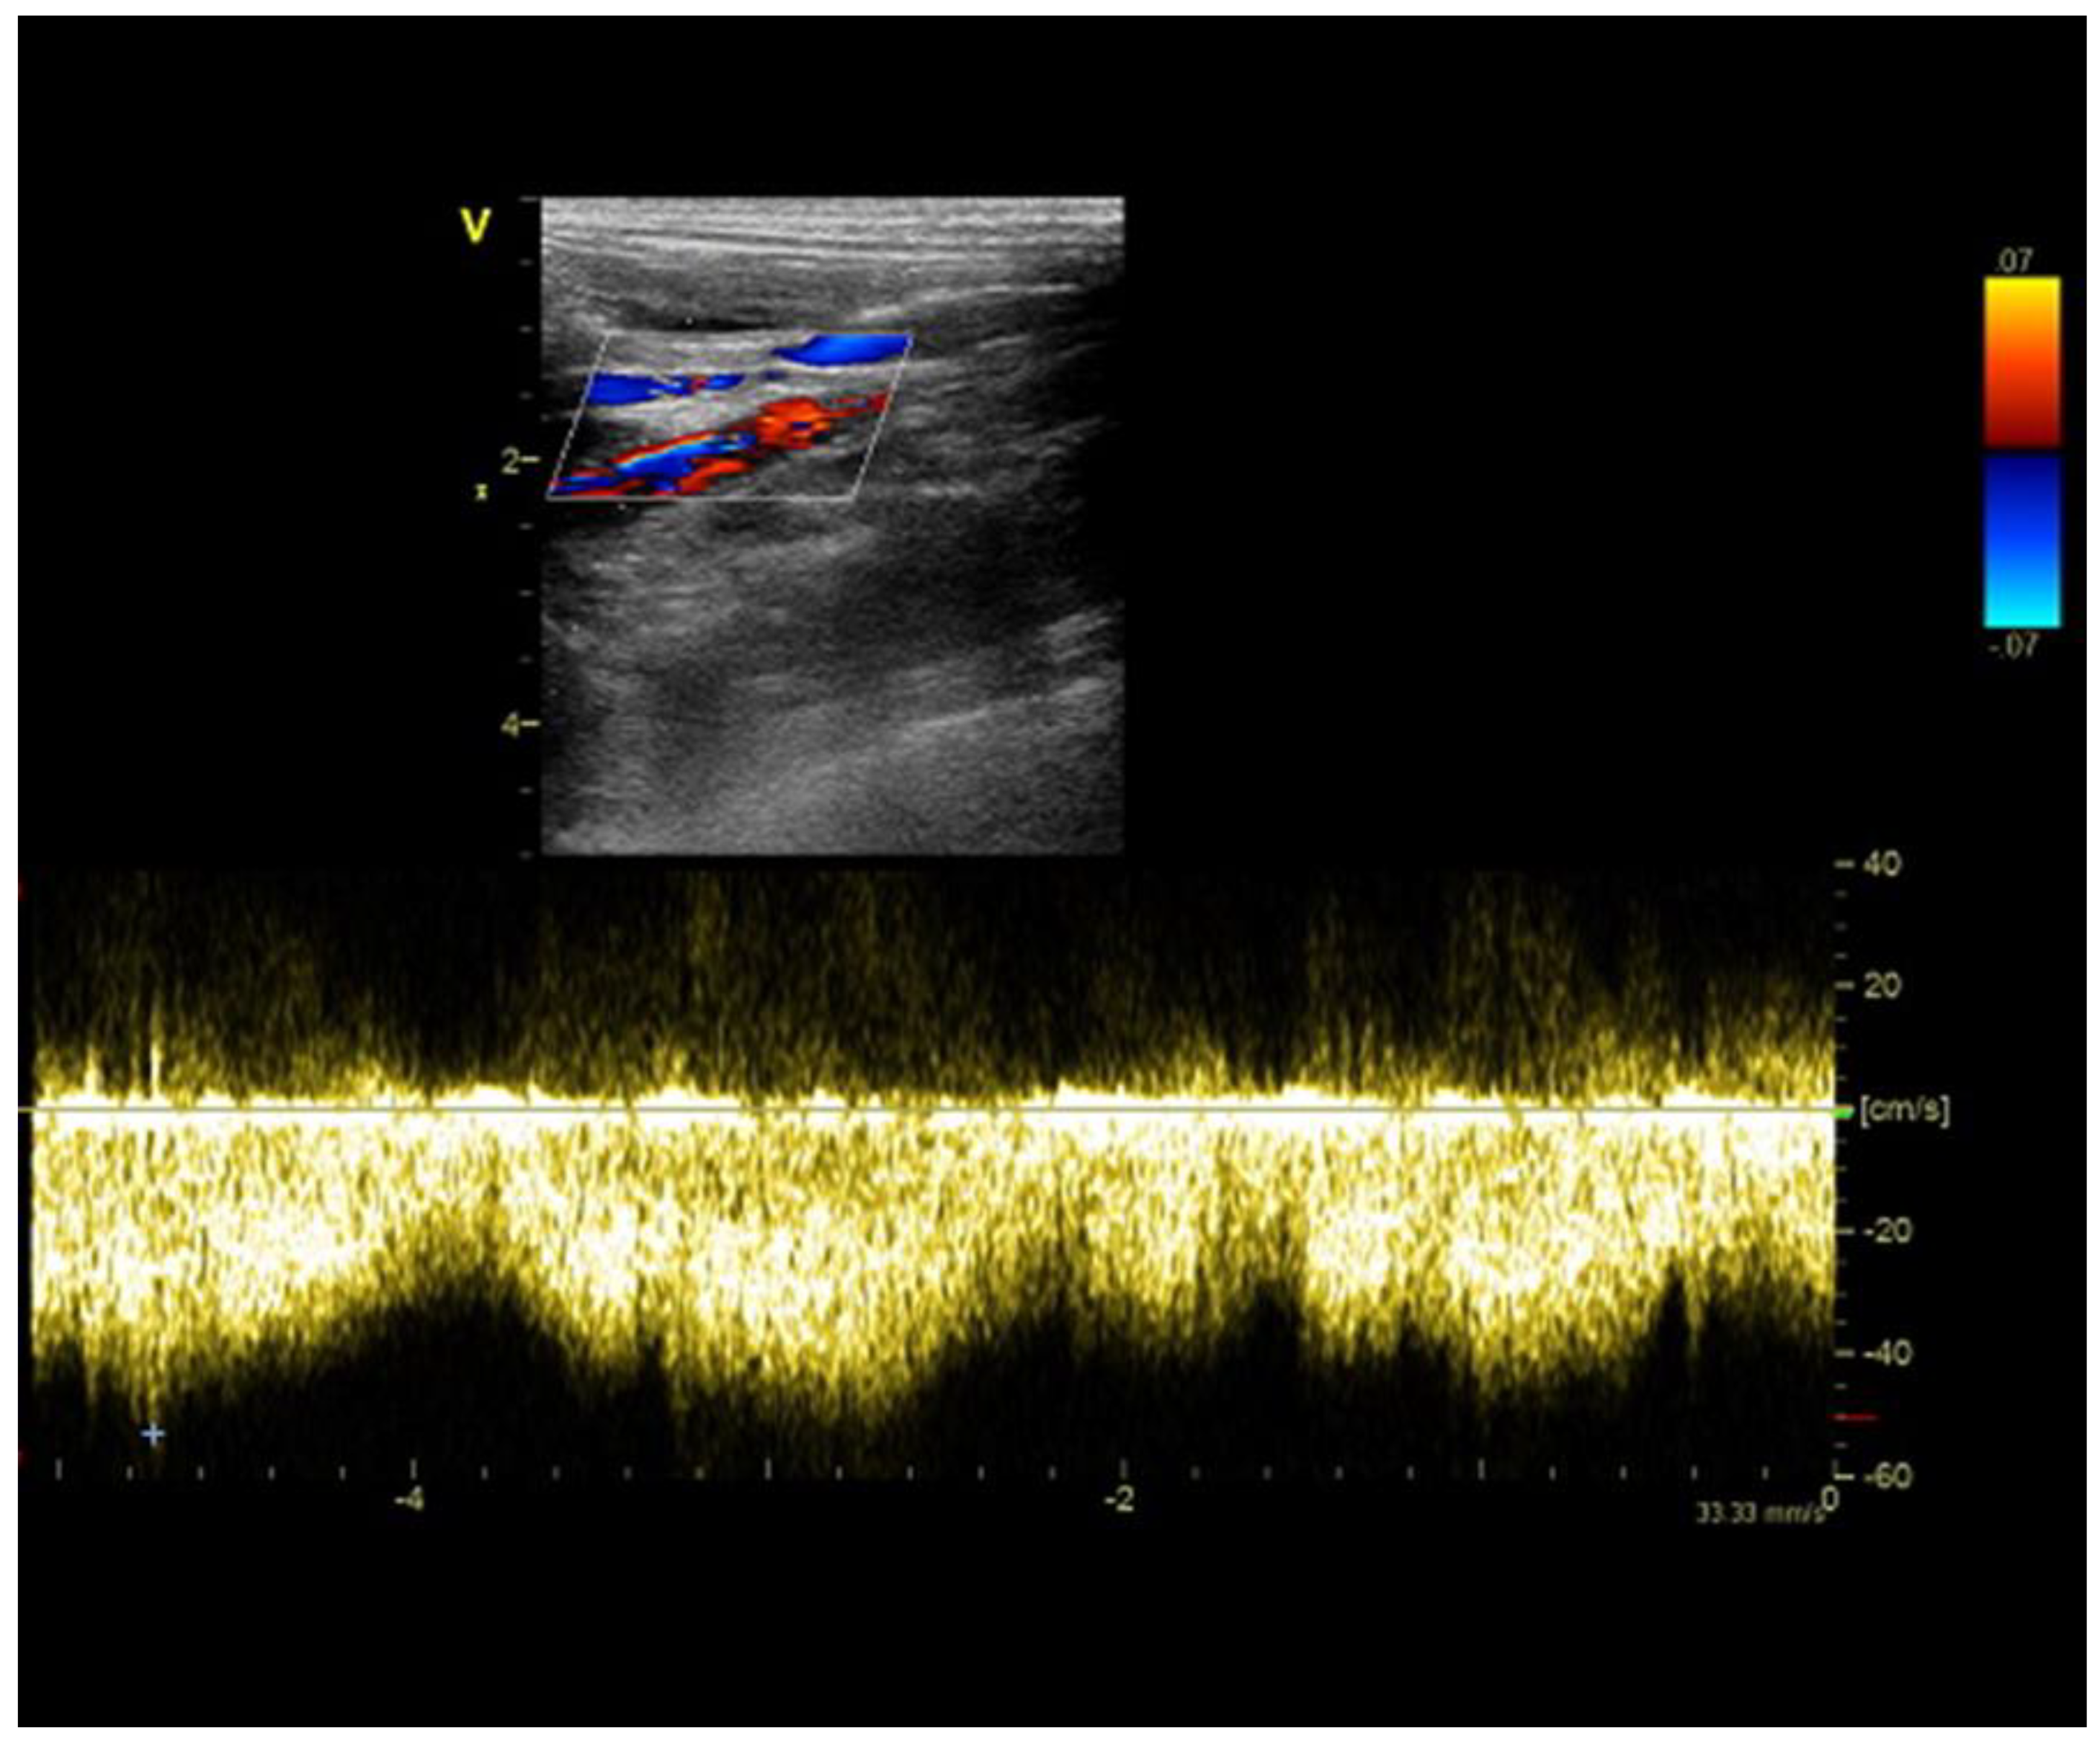

2.3. Case C (Dog)

2.4. Case D (Dog)

2.5. Case E (Cat)